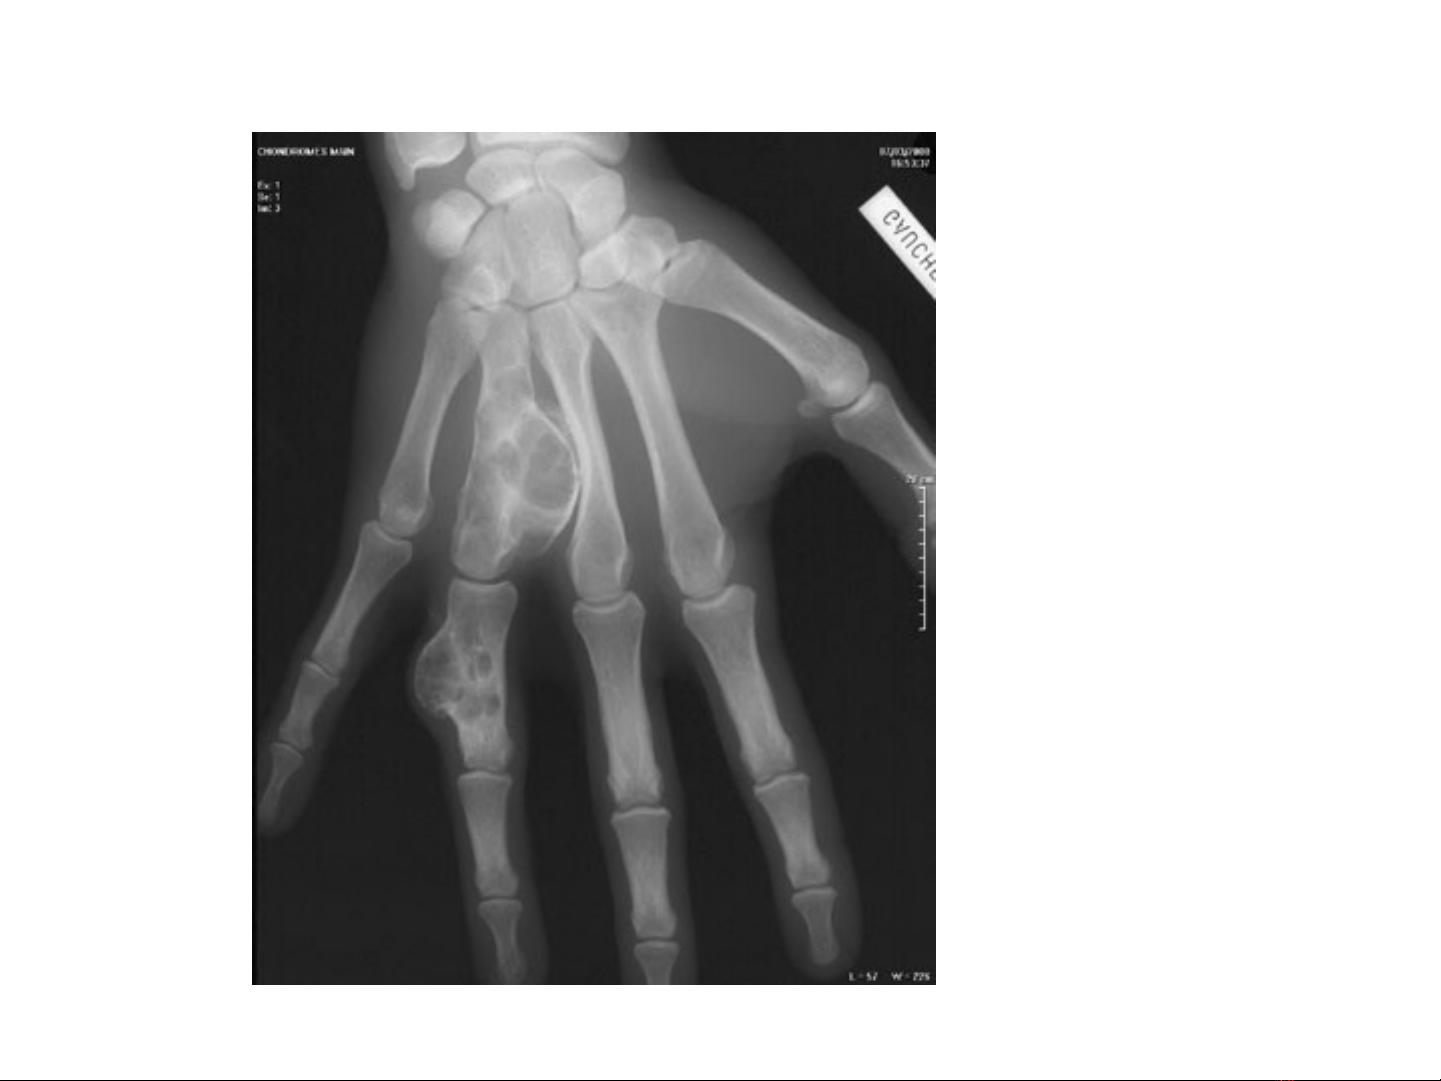

1.3 U sụn

U sụn thương tiềm tàng , đôi khi phát hiện

khi xương bị gãy , u sụn thường đơn độc .

Số ít trường hợp có ở nhiều nơi , hay xuất

hiện ở đốt ngón tay ngón chân , ở xương dài

Vì tổ chức sụn không cản quang , nên u sụn

biểu hiện bằng vùng không cản quang tròn hay

bầu dục thường ở trung tâm , đồng đều hay lấm

tấm những hình vôi hoá nhỏ , có bờ viền rõ với

hình vỏ xương mỏng và thườn xương có hình bọt ,

đôi khi u sụn có vách ngăn thành ô nhỏ như trong

kén xương